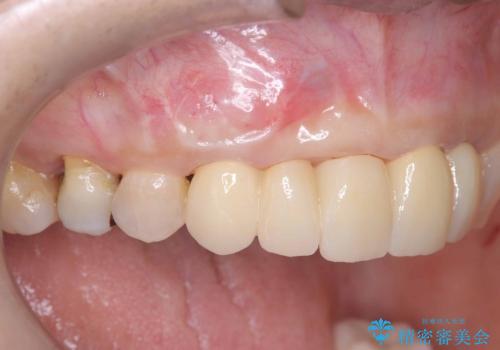

抜歯即時インプラントには、切開量が少なく痛みが出にくいこと、一度の手術で治療が完了するため治療期間を短くでき、患者様の身体的負担も軽減できるという大きなメリットがあります。

今回のケースでも、しっかりと固定が得られたため、手術は1回で終了し、短期間でオールセラミッククラウンまで装着することができました。患者様も術後の痛みはなく、処方した痛み止めも服用されなかったとのことです。

これだけ大きな病変があったにもかかわらず、痛みがなく短期間で治療が終わったことに加え、被せ物の色も周囲の歯に調和し美しく仕上がったことに、大変ご満足いただけました。